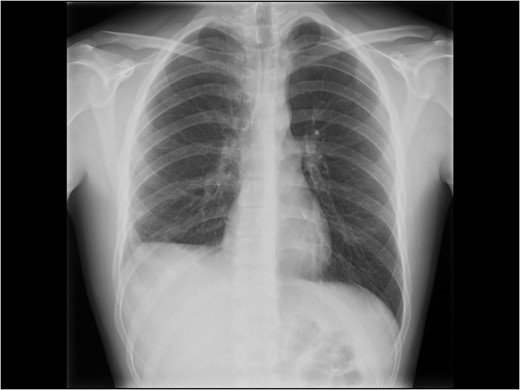

Due to the delayed presentation and concomitant presence of a subacute liver injury with fragile tissue, the decision to delay elective treatment of the diaphragm was made. The patient was admitted 8 weeks later for elective repair. An initial laparoscopic approach was attempted, but was converted to open repair by an inverse L subcostal incision due to the size of the defect and adhesions of diaphragmatic edges on surfaces to the liver. In addition there were pulmonary adhesions to the posterior liver surface (Fig. 3A). Adhesiolysis was performed of the diaphragmatic defect to the liver. A double lumen ventilation tube allowed for deflating of the right lung and gentle dissection of the pulmonary adhesions to the liver. Considerable loss of tissue domain of the diaphragm due to retraction and fibrosis was noted (Fig. 3B) for a grade V diaphragm injury (Table 1) based on the AAST score [5]. The size of the defect, measured as 10 cm × 5 cm (50 cm2) prevented primary suture repair of the diaphragm in an end-to-end fashion. Thus, a 1 mm thick Gore-Tex™ patch was used to cover the defect (Fig. 2A) and a pulmonary drain was placed (Fig. 4B). The patient recovered uneventfully, the chest drain was removed on post-operative Day 2 and he was discharged on post-operative Day 6 with a recommendation not to resume full physical activity until 2 months after surgery. When he was seen in the outpatient clinics 3 months later postoperatively, he had resumed full physical activity including sports. He had no complaints and had a well-healed scar. An erect chest X-ray showed a moderately high-standing diaphragm on the right side (Fig. 5).

Chest X-ray at follow-up. Still some degree of diaphragm high-stand on the right side.